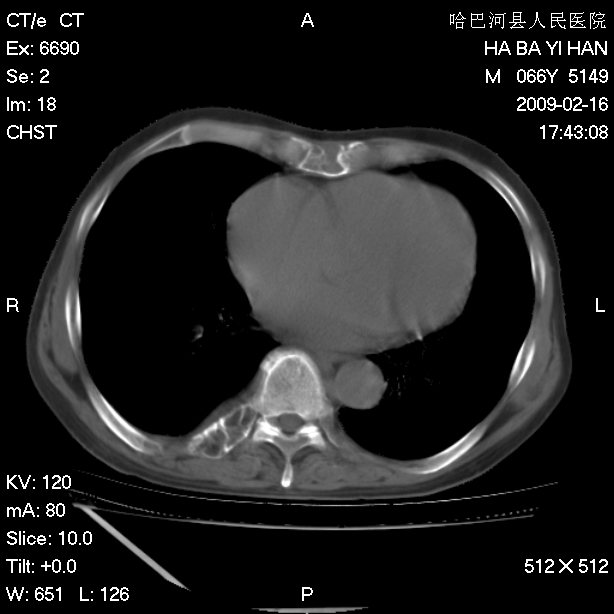

以下是引用huangxun4321在2009-2-16 20:18:00的发言:[br]部分病灶可见硬化边,部分可见骨质破坏消失,部分病灶内可见骨脊,说明病灶内既有良性病变,又有恶性病变,考虑骨巨细胞瘤恶变,未除骨纤恶变,畸形性骨炎少见,亦要考虑.

以下是引用731208在2009-2-16 20:31:00的发言:[br]考虑恶性胸膜间皮瘤并肋骨,脊柱转移。

以下是引用yijiansheng在2009-2-16 20:16:00的发言:[br]考虑恶性胸膜间皮瘤并肋骨,脊柱转移。

以下是引用形影不离在2009-2-16 19:55:00的发言:[br]考虑多发性转移瘤。